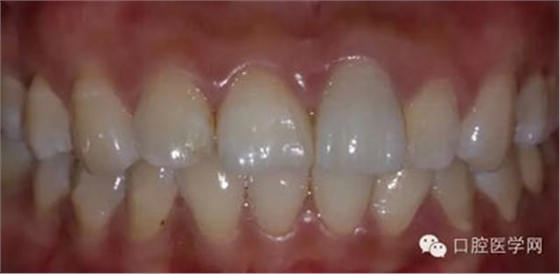

5、3MU200樹脂粘接劑粘固全瓷冠術(shù)后照

6、術(shù)后一周照,牙齦恢復(fù)良好